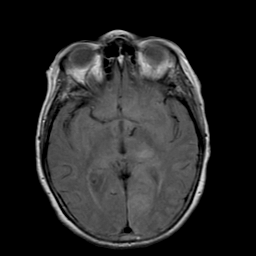

Stroke: proton density-weighted MR #2 -- Slice #11

[Home][Help][Clinical] Slice 11